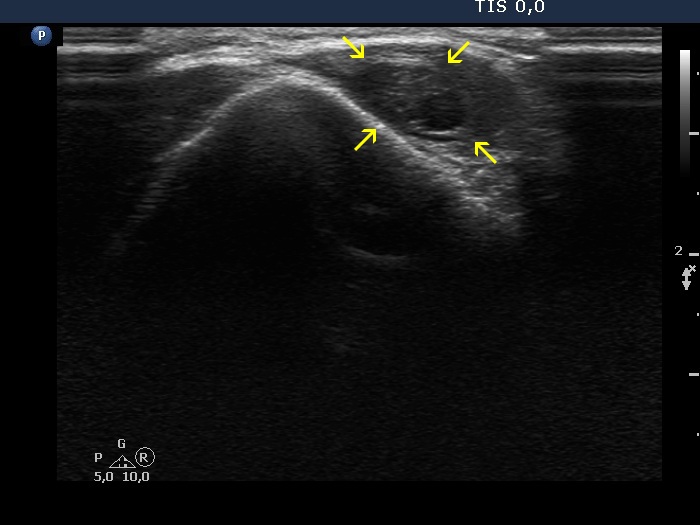

Eleven years after the surgery (ultrasonographic picture 5b)

A few cm above the left thyroid bed, transverse scan. The cystic mass is signed with yellow arrows.